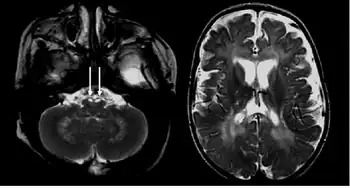

Diagnosis

There are a few ways to help pinpoint the presence of Krabbe disease. Newborn screening for Krabbe disease includes assaying dried blood cells for GALC enzyme activity and molecular analysis for evidence of GALC enzyme mutations. Infants displaying low enzyme activity and/or enzyme mutations should be referred for additional diagnostic testing and neurological examination.[11] 0-5% GALC enzyme activity is observed in all symptomatic individuals with Krabbe disease.[6] High concentration of psychosine in dried blood spots may also be identified as a marker for Krabbe disease.[12] A 2011 study discovered that individuals with Krabbe disease, more so in later-onset individuals, tend to have an abnormal increase in CSF protein concentration.[13]

The disease may be diagnosed by its characteristic grouping of certain cells (multinucleated globoid cells), nerve demyelination and degeneration, and destruction of brain cells. Special stains for myelin (e.g., luxol fast blue) may be used to aid diagnosis.